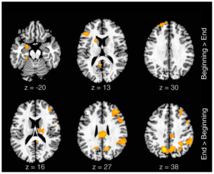

Actividad neuronal relacionada con la improvisación lírica. Fuente: Scientific Report.

Las mediciones de la actividad cerebral de los raperos en ambas actividades demostraron que, durante la interpretación de rap improvisado, se produjo un aumento en la actividad neuronal de la corteza prefrontal medial, una región del cerebro responsable de la motivación para el pensamiento y la acción.

Asimismo, en esta tarea pudo constatarse una disminución de la actividad neuronal en la corteza dorsolateral prefrontal, un área del cerebro que normalmente desempeña la función de supervisión y control.

Las mediciones de la actividad cerebral de los raperos en ambas actividades demostraron que, durante la interpretación de rap improvisado, se produjo un aumento en la actividad neuronal de la corteza prefrontal medial, una región del cerebro responsable de la motivación para el pensamiento y la acción.

Asimismo, en esta tarea pudo constatarse una disminución de la actividad neuronal en la corteza dorsolateral prefrontal, un área del cerebro que normalmente desempeña la función de supervisión y control.

Por otra parte, los científicos constataron que la improvisación también incrementó la actividad cerebral en el llamado “sistema perisilviano” del cerebro, que participa en la producción del lenguaje; en la amígdala (zona del cerebro relacionada con la emoción), y en las áreas motoras cinguladas.

Por otra parte, los científicos constataron que la improvisación también incrementó la actividad cerebral en el llamado “sistema perisilviano” del cerebro, que participa en la producción del lenguaje; en la amígdala (zona del cerebro relacionada con la emoción), y en las áreas motoras cinguladas.